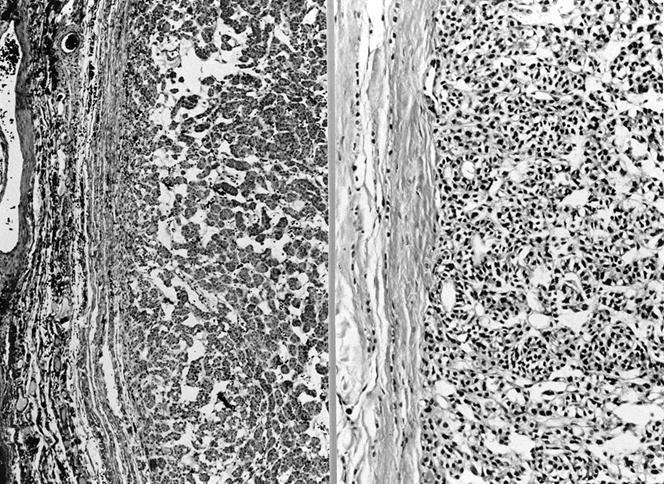

Microscopic (histologic) images

Contributed by Shipra Agarwal, M.D., Andrey Bychkov, M.D., Ph.D., Mark R. Wick, M.D., Asmaa Gaber Abdou, M.D. and AFIP

Patterns:

Microscopic (histologic) description

- Architecturally and cytologically different from surrounding gland

- Compression signs in surrounding thyroid tissue

- Encapsulated; thin or moderately thick capsule

- Architectural patterns (can be seen in any combination)

- Normofollicular (simple): size similar to normal thyroid follicles

- Microfollicular (fetal): smaller follicles, small amount of intraluminal colloid

- Macrofollicular (colloid): large follicles, flattened epithelium, abundant colloid

- Solid / trabecular (embryonal): minimal or no colloid

- Focal papillary pattern, occasionally; especially in hyperfunctioning adenoma and follicular adenoma with papillary hyperplasia

- Cuboidal to low columnar cells

- Small round nuclei, smooth nuclear boundary, uniformly hyperchromatic or euchromatic, dense chromatin, absent nuclear features of papillary thyroid carcinoma, nuclear score 0 or 1 (JAMA Oncol 2016;2:1023)

- Inconspicuous nucleoli

- Rarely, lipid filled vacuoles in cytoplasm

- Mitoses are uncommon

- Scant stroma

- Secondary changes: fibrosis, hyalinization, hemorrhage, hemosiderin deposition, edema, cystic degeneration, calcification, osseous or cartilaginous metaplasia